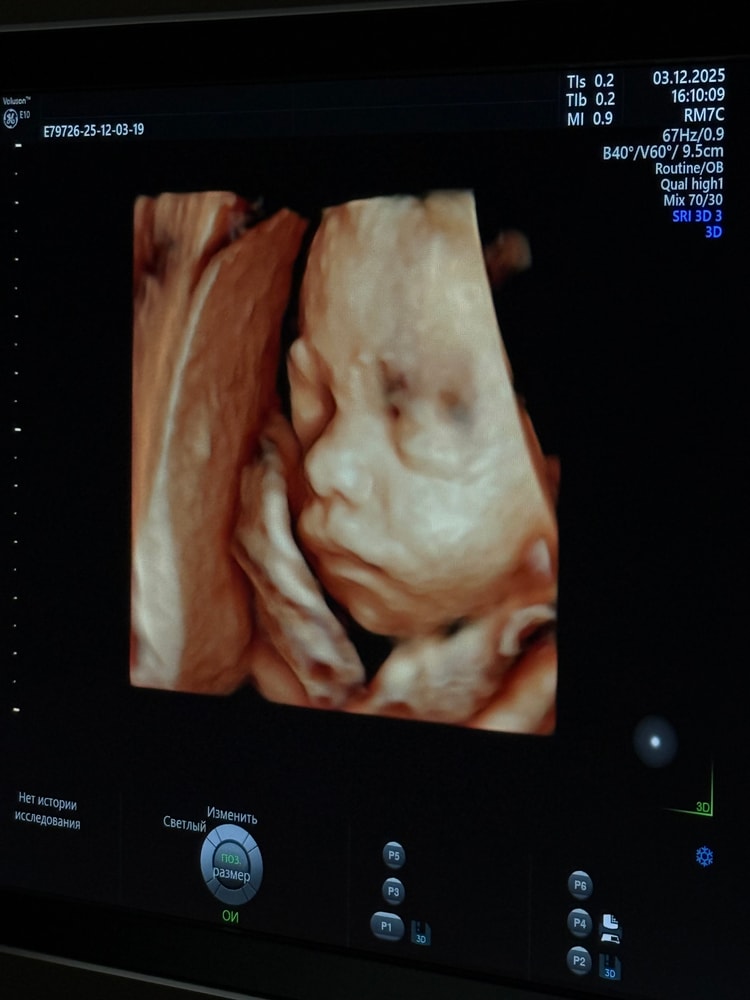

сегодня на узи в 26 недель нет кист, нос 7 мм, и вот такое фото в 3d, жду родов и верю что все будет хорошо ❤️